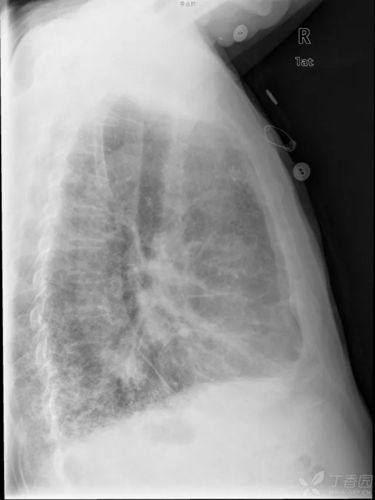

秒懂胸片!扒一扒胸片的基础知识

秒懂胸片扒一扒胸片的基础知识

正常胸片图片图解

胸片正常图片

正常胸片图

正常胸片影像图片

正常胸片

胸片怎么看